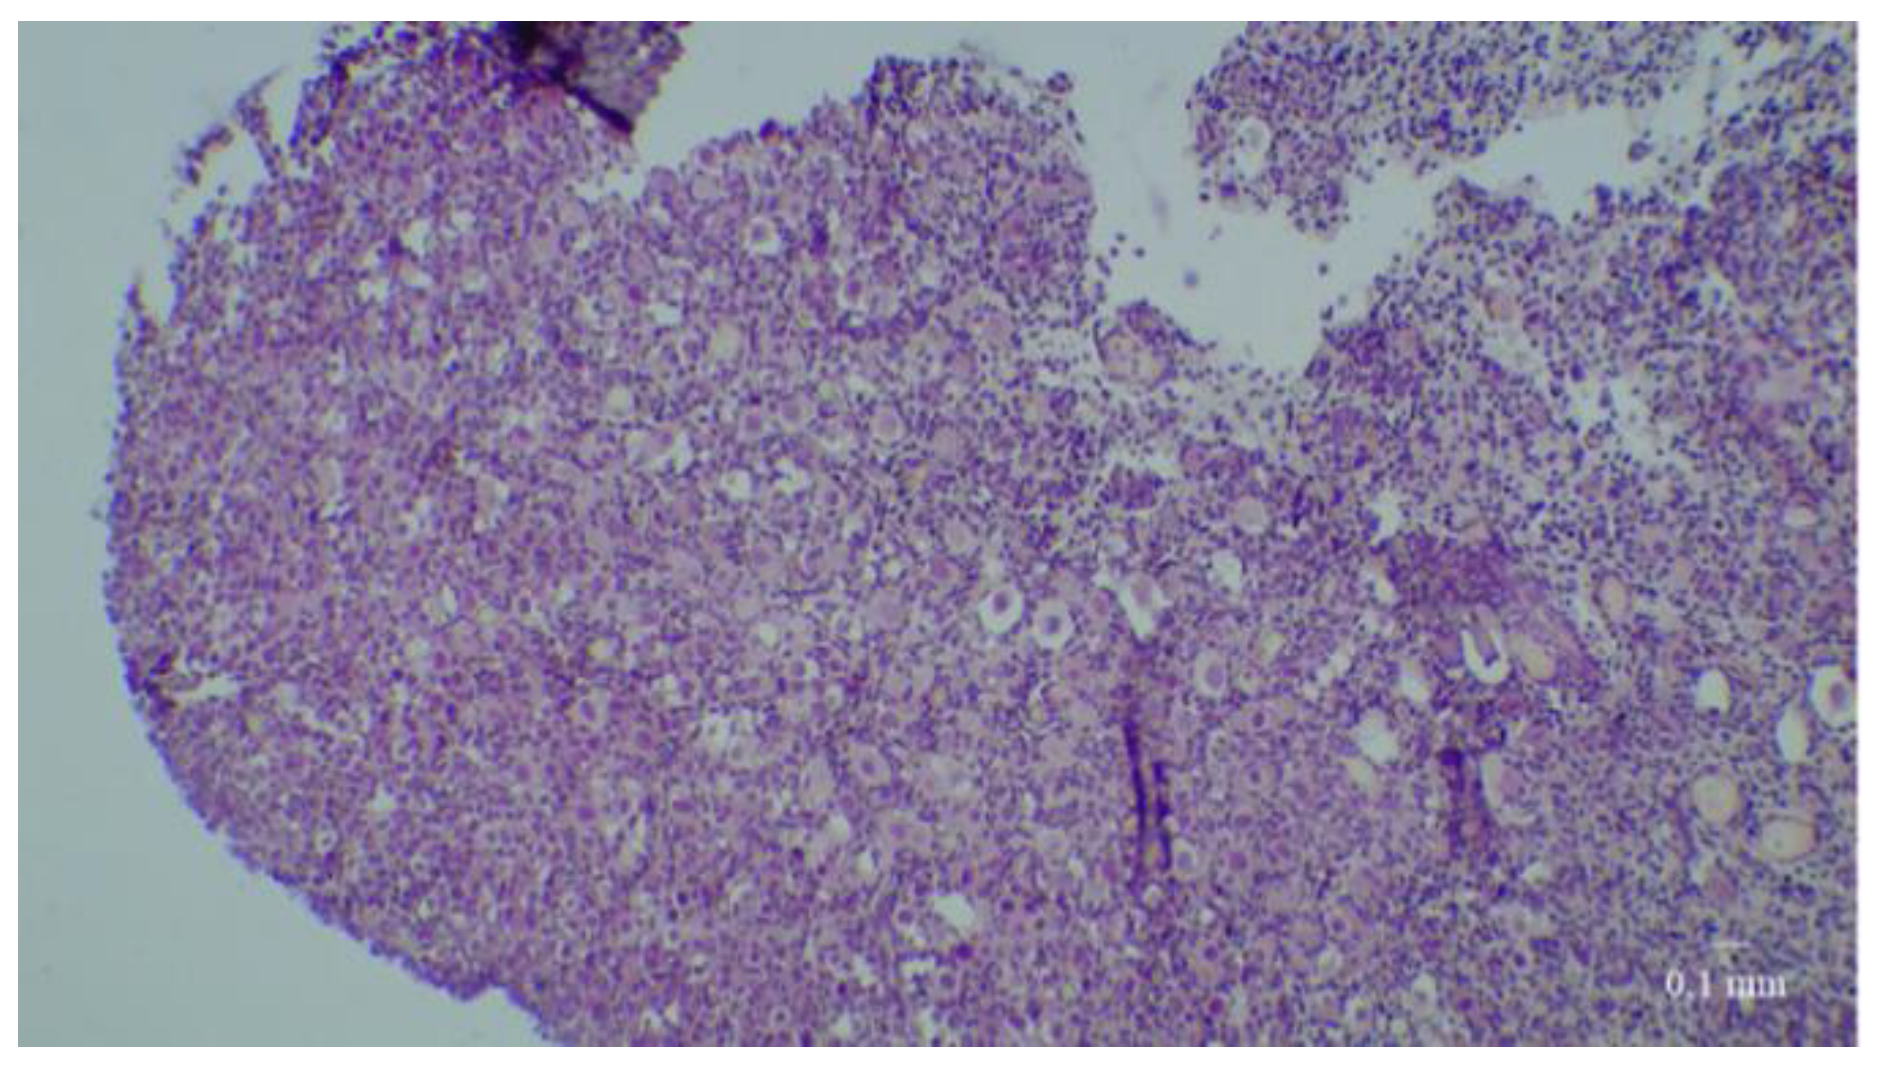

2.4. Histological Analyses

3.3. Immunostaining for Cell Apoptosis